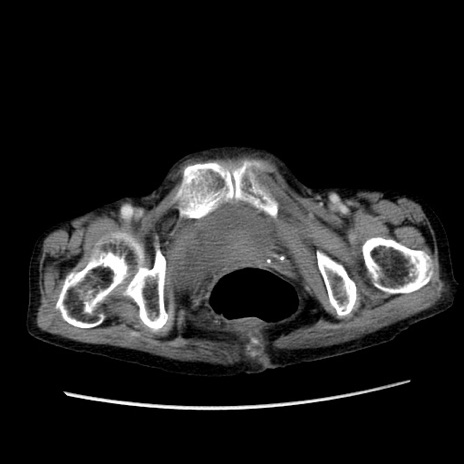

冠状断像